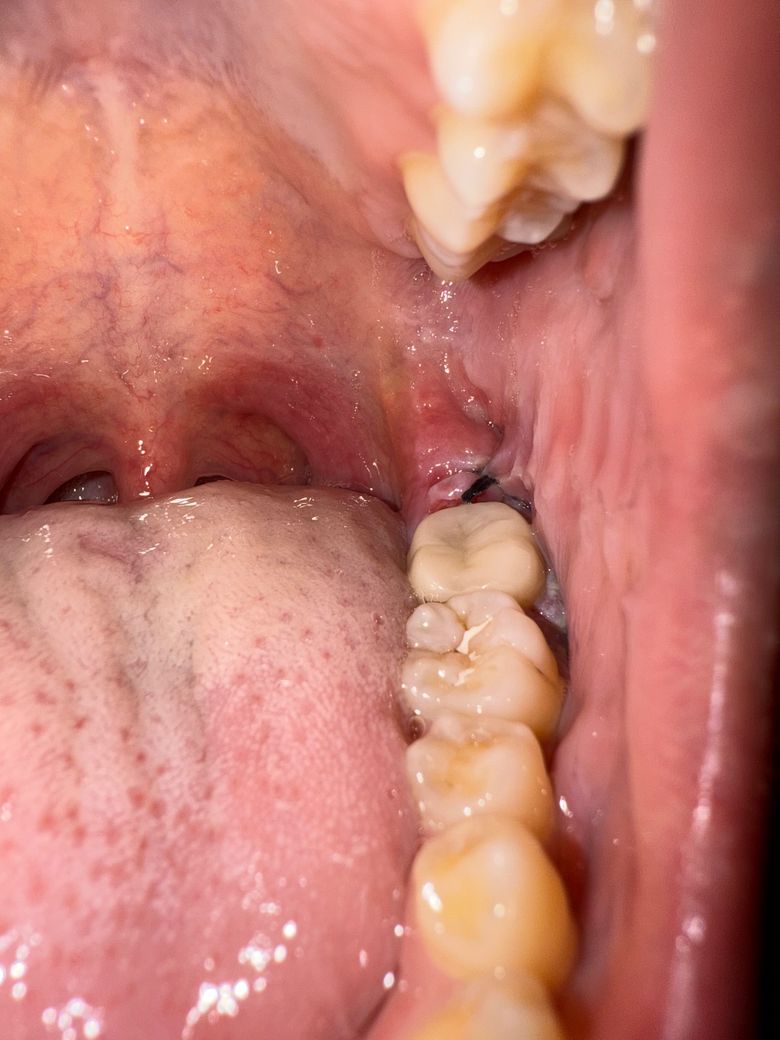

사랑니 발치 4일차에서의 출혈과 합병증 가능성

사랑니 발치 4일차인데 2번째 사진 부분에서 출혈이 조금있고 통증이 아직 있는데 드라이소켓이 될만한 부분이나 안 좋은 부분들이 있을까요

사진을 봤을 경우에는 발치한 부위의 잇몸이 잘 봉합되어 잇고 출혈도 커보이지는 않습니다.

발치부위가 아주 명확히 보이진 않으나 저정도면 특별히 치유에 문제가 있는 상황은 아닐 것 같습니다.